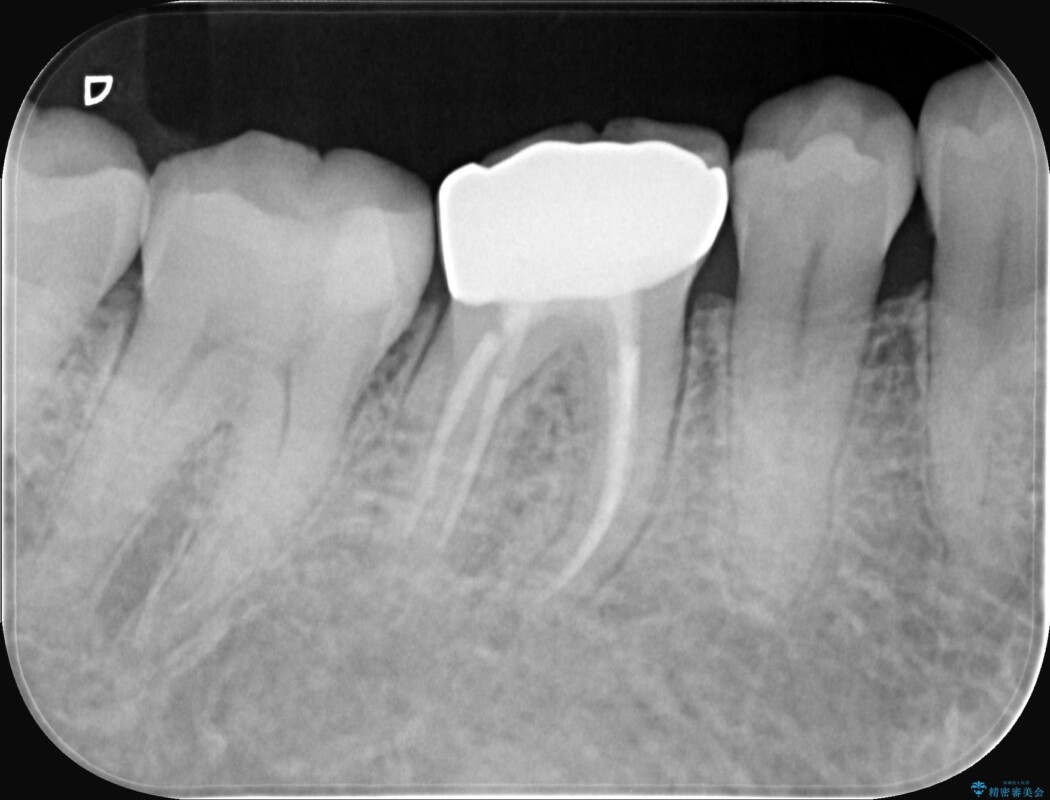

精密検査の結果、根の先に大きな病変が認められますが、根管内が狭窄し湾曲しているため、非常に難易度の高いケースです。

通常の治療器具では奥まで届かず、そのままでは再発や抜歯になるリスクが高いため、マイクロスコープを使用して根の奥まで精密に清掃・殺菌し、歯を残すための治療計画を立てました。

術後の経過は非常に良く、あんなに大きかった膿の袋は消え、健康な骨が再生しているのが確認できました。痛みや腫れも消えて抜歯を免れ、現在は被せ物を入れてしっかりお食事を楽しんでいただけるようになっています。